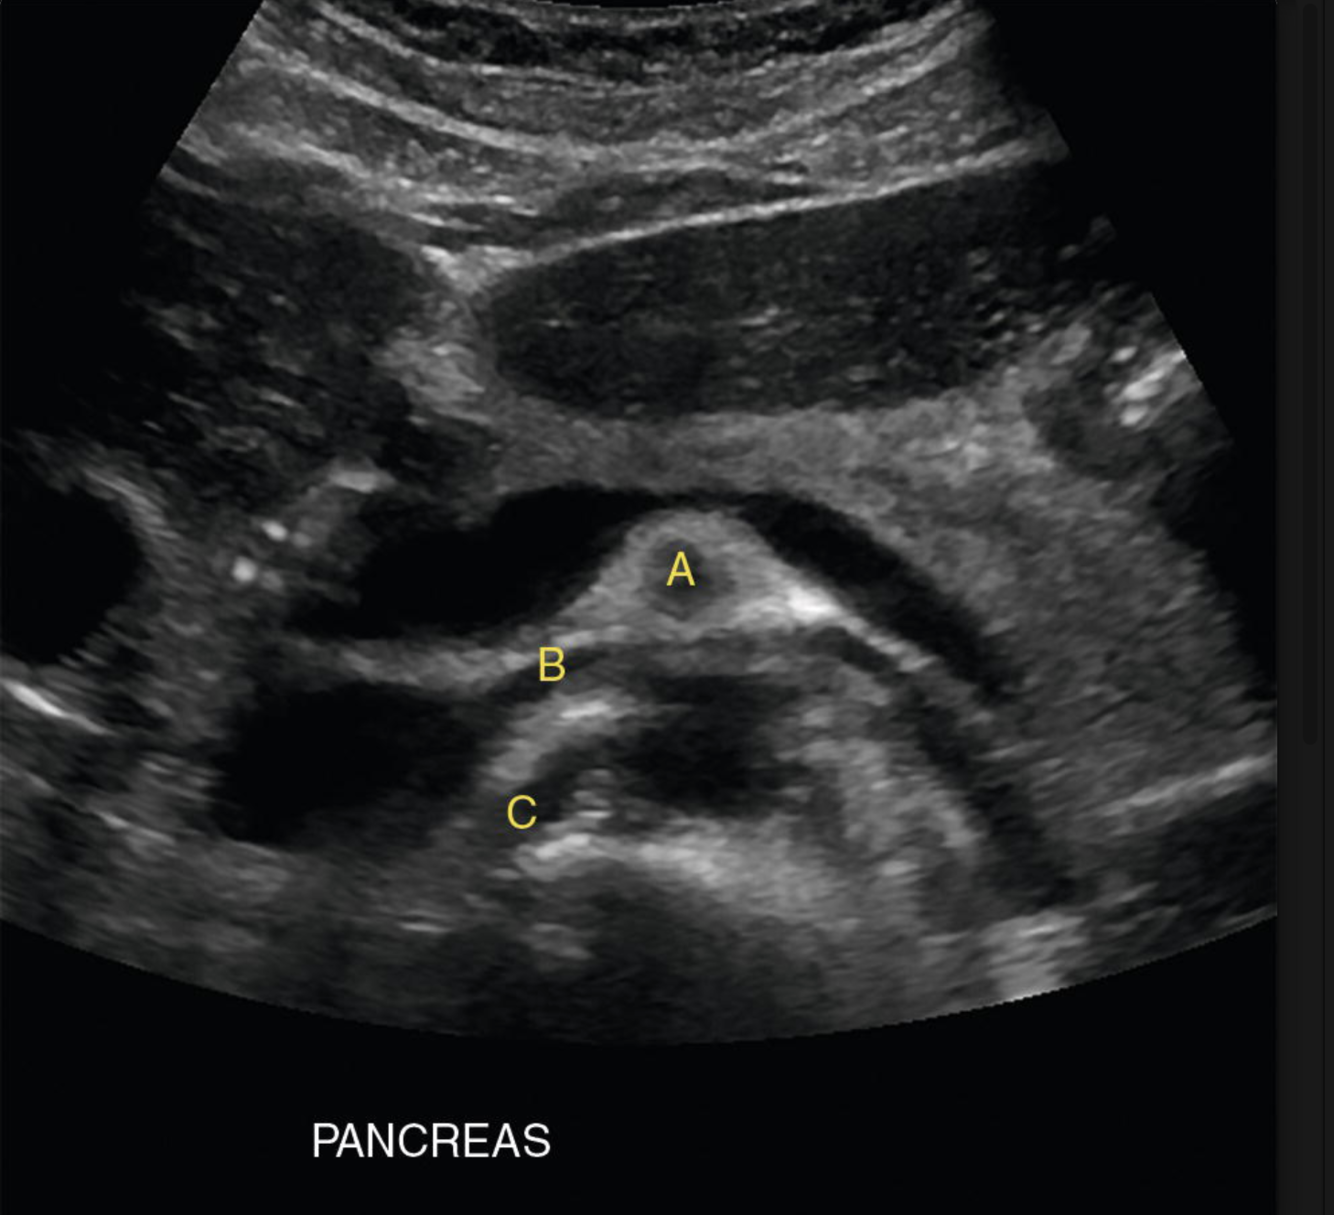

Most common cause of this?

“Double duct” sign = pancreatic adenocarcinoma at the pancreatic head.

Identify the following structures:

A: SMA

B: L renal vein

C: R renal artery